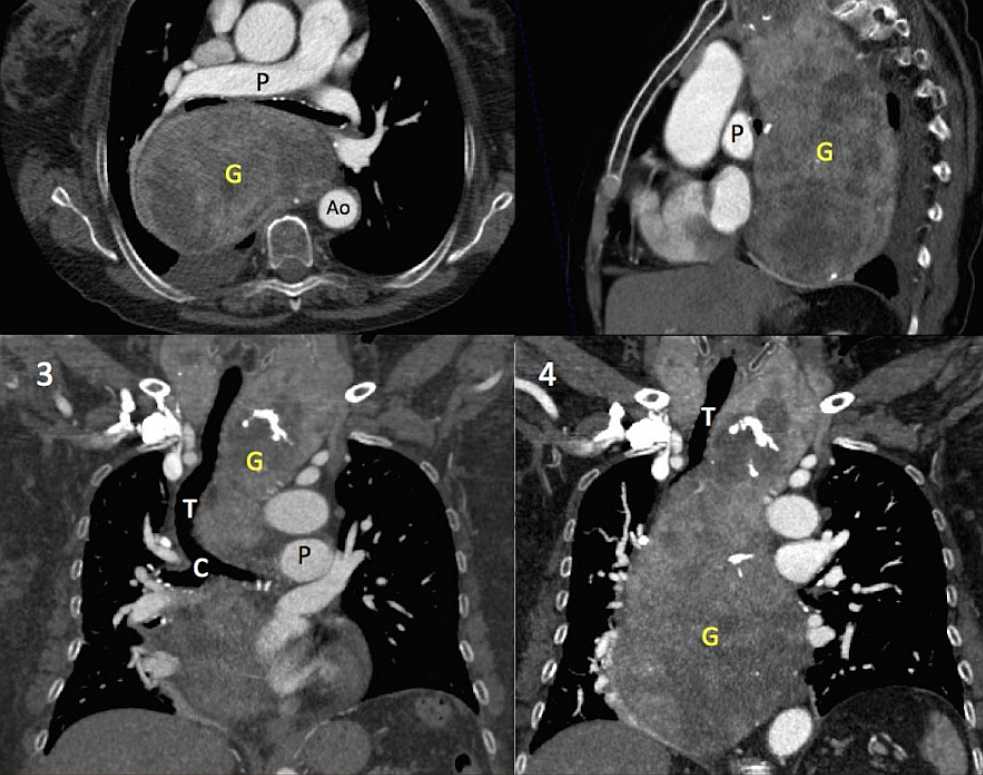

A contrast-enhanced chest CT revealed a large heterogeneously enhancing soft tissue mass (20 x12x9 cm) with calcifications extending from the cervical region to the right hemidiaphragm (white arrows in figure 2.2 and 2.4). It caused compression and deviation of the trachea, carina, oesophagus and vascular structures.